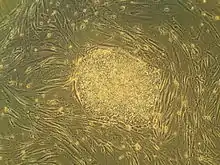

Stem cells are cells that can differentiate to become different types of cells.[15] The hope is that stem cells transplanted into an injured area of the spinal cord will allow neuroregeneration.[6] Types of cells being researched for use in SCI include embryonic stem cells, neural stem cells, mesenchymal stem cells, olfactory ensheathing cells, Schwann cells, activated macrophages, and induced pluripotent stem cells.[1] When stem cells are injected in the area of damage in the spinal cord, they secrete neurotrophic factors, and these factors help neurons and blood vessels to grow, thus helping repair the damage.[16][17][18] It is also necessary to recreate an environment in which stem cells will grow.[19]

Embryonic stem cells (ESCs) are pluripotent; they can develop into every type of cell in an organism, such as oligodendrocytes. .[6]Oligodendrocytes and motor neurons have been predicted to be a favorable target for ESCs regarding treating neurological disorders and traumas.[25] After a SCI takes place there is evidence of oligodendrocytes degradation, eventually leading to cell death. This results in a lack of myelination, which enhances signals sent amongst neurons, causing disfunction in signaling. A potential solution could be hESC-derived oligodendrocyte transplantation; however, the success of this process depends off the cell’s ability to differentiate towards neural cell types in vitro. This is where more testing and research is being conducted using animal models.